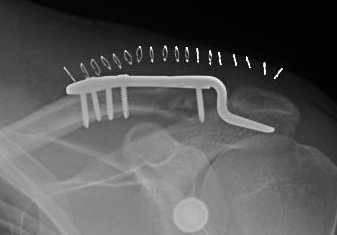

Hook plate versus locking plate

- systematic review of 523 patients

- comparison hook plate and dorsal locking plate

- mean 3 year follow up

- no difference in outcome scores

- better reduction with hook plate

- increased nonunion with locking plate

- increased complications with hook plate

Hook Plate

Advantage

Mechanically secure

Disadvantage

Needs to be removed

- subacromial impingement

- acromial erosion

- shoulder stiffness

Technique

Synthes surgical technique PDF

AO surgery reference hook plate technique

Lazy beachchair

- tilt head away

- split delto-trapezius fascia to expose clavicle

- clean and reduce fracture

- detach trapezius from medial acromion to facilitate hook passage under acromion

- trial different hook depths +/- image intensifier

- avoid over-reduction / insufficient hook depth increases risk of acromial erosion

Results

- 36 patients with displaced distal clavicle fractures treated with hook plate

- 95% union rate

- mean time to union 3 months

- hook plate removed in 92%

- 2 patients presented with late falls and fractures medial to the plate

- 35 patients with displaced distal clavicle fractures treated with hook plate

- 100% union rates

- 23% shoulder stiffness

- 17% subacromial erosion

Complications

Hook not under acromion Periprosthetic fracture